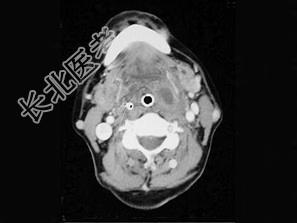

- 单项选择题患者,男性, 23岁,发热头痛3天, 伴咽旁和颈部剧痛,吞咽困难, 吐字不清,查体: 扁桃体及咽侧壁突向咽腔,但无明显充血, CT检查结果如下图:患者最可能的诊断为 ( )

A、咽旁脓肿

B、扁桃体周脓肿(前上型)

C、扁桃体周脓肿(后上型)

D、咽后脓肿

E、以上都不是